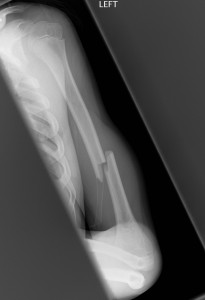

Shaft Fractures

- Transverse fractures generally occur from a direct blow and spiral fractures from a twisting mechanism.

Above: Complete fracture of shaft of humerus with mild displacement

Above: Spiral fracture of shaft of humerus